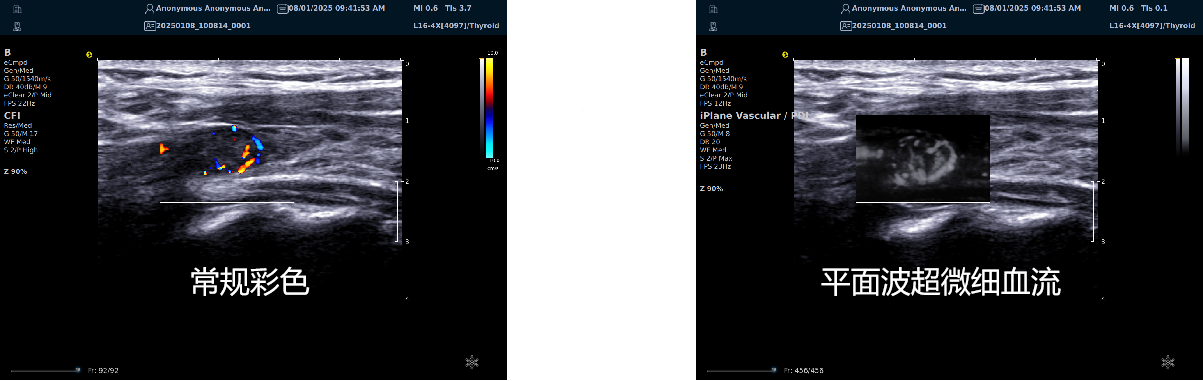

平面波超微细血流显像

能够提供更多真实的组织细小及末梢血管的血流信息,直观的观察组织内部的血管架构及血流形态的情况,提供临床更多有价值的诊断信息。

临床应用:

肿瘤鉴别诊断(肝脏、肾脏、甲状腺、乳腺、 涎腺等)

淋巴结评价(炎症、肿瘤)

肌骨系统临床诊断和疗效监测(关节、滑膜、韧带、肌肉炎症、 损伤等)

斑块内新生血管评估

超声介入术前进针方案提供血流参考信息

超声介入术后疗效评估